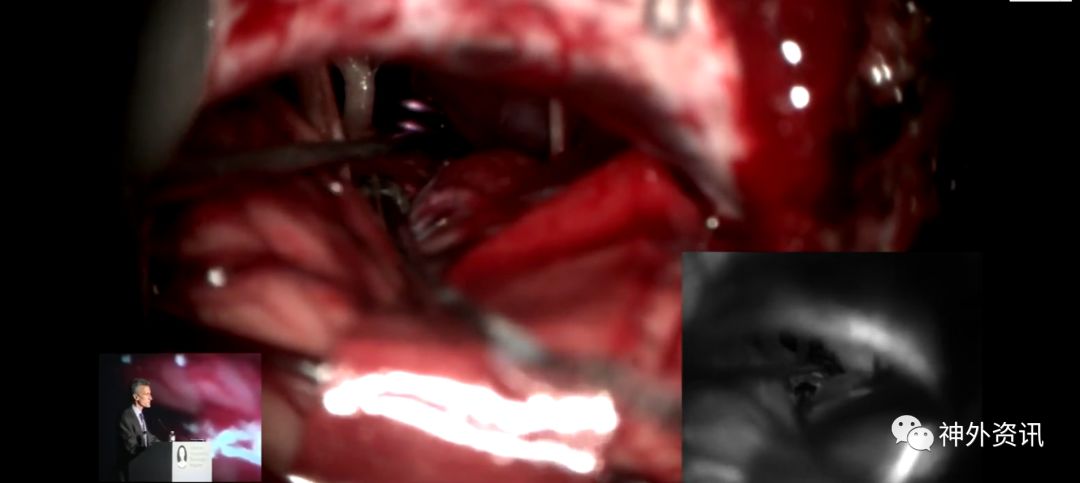

Michael T. Lawton,巴洛神经科学研究所(BNI)主席,精于各种脑血管疾病的治疗,已累及外科治疗4400余例颅内动脉瘤和700余例AVM,发表论文270余篇,参编书籍40余部,著有《Seven Aneurysms: Tenets and Techniques for Clipping》。